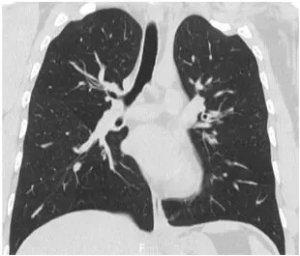

Dupilumab effective for refractory asthma complicated by recurring chronic eosinophilic pneumonia

Dupilumab promising treatment for refractory asthma complicated…